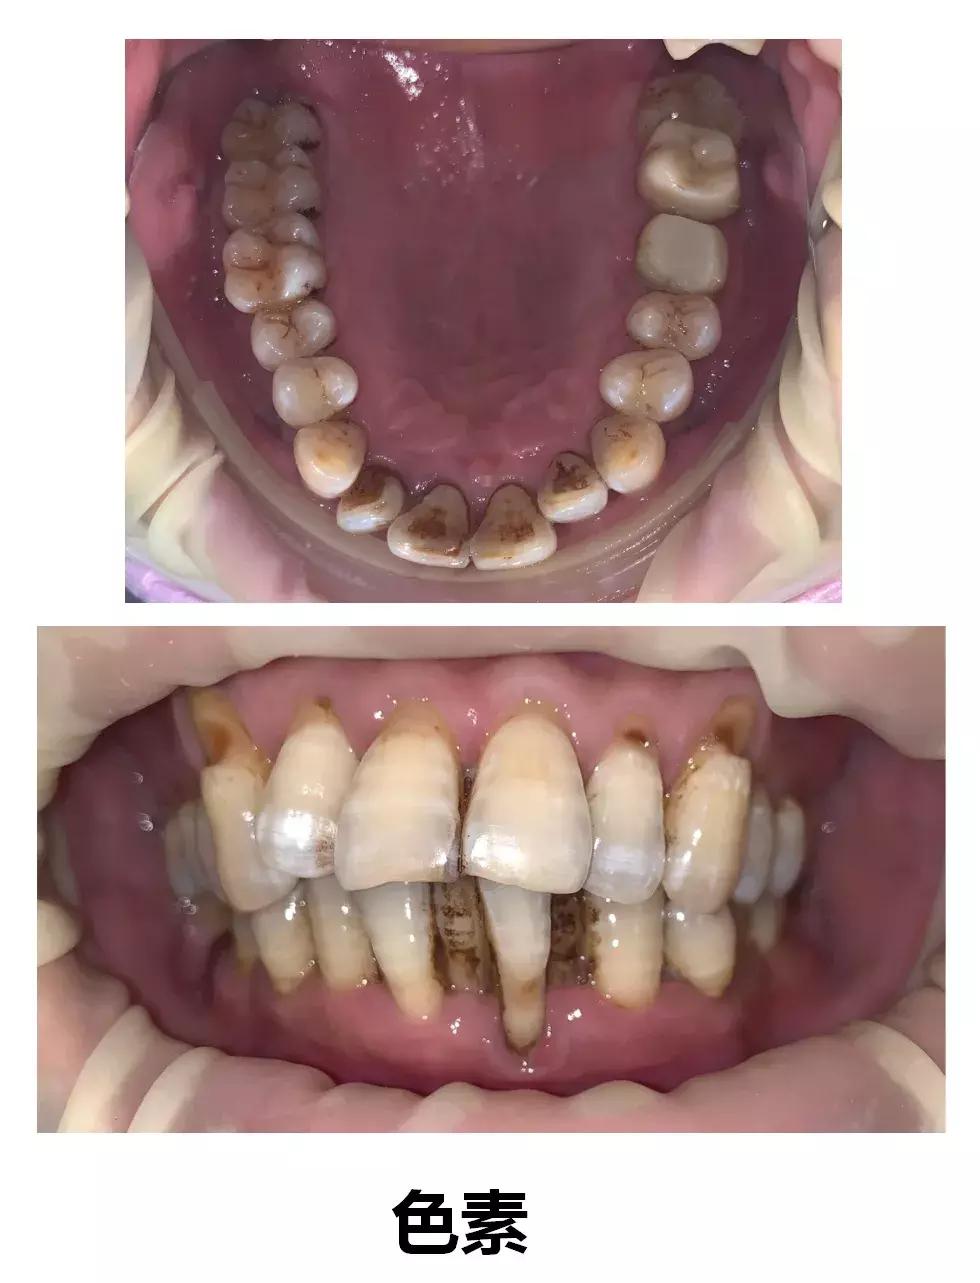

第三种可能是单纯性色素沉着,主要是色素长期附着在牙面的菌斑上,没有渗透到“牙齿内部”,这种情况可以通过洗牙来处理。

图片来源网络